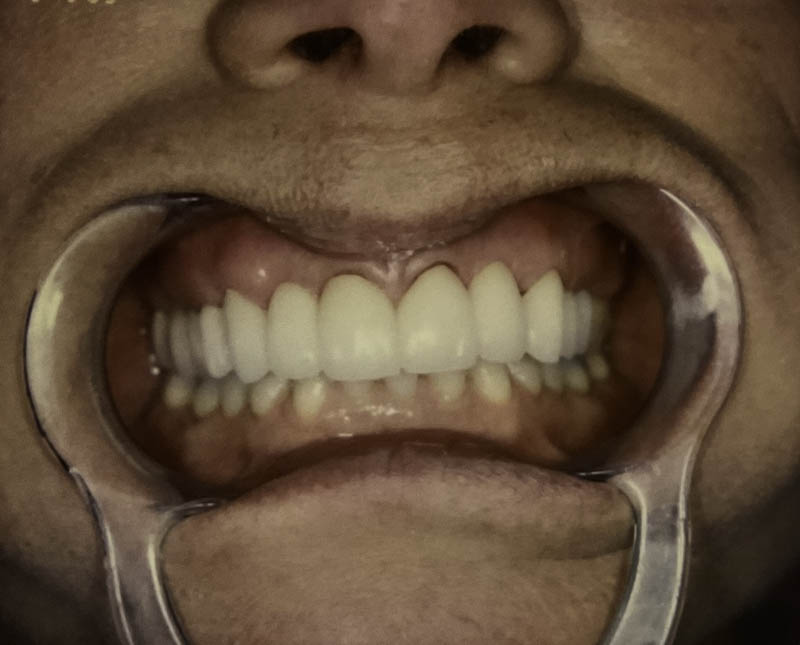

Before

After

Cosmetic Crowns

Case Highlight